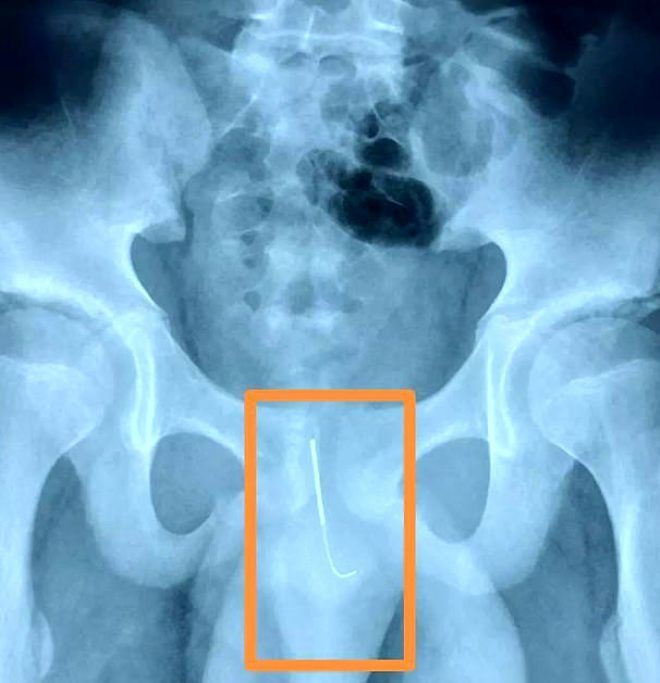

ÇİN 'in Shaanxi eyaletine bağlı Xi şehrinde 12 yaşındaki bir erkek öğrenci, ödevini yetiştirirken uyuyakalmamak için cinsel organının içine 11 santimlik bir akupunktur iğnesi koydu. Ertesi gün çocuğunun yürümekte zorlandığını gören anne, oğlunu hastaneye götürdü ve korkunç gerçeği öğrendi.

Utandığı için ailesine söylemedi

Adı Xiaolong olarak açıklanan çocuk, annesine ödevini yetiştirmek zorunda olduğu için uyanık kalması gerektiğini, bu yüzden böyle bir yola başvurduğunu söyledi. Doktorlar, öğrencinin yaptığı şeyden utandığı için ailesine söylemekten çekindiğini, bu yüzden cinsel organındaki iğne ile 15 saat durduğunu ve iğnenin idrar torbasına çok yakın olduğunu belirtti.

İki saat süren bir ameliyattan sonra doktorlar iğneyi çıkarmayı başardı

Öyle ki, iğnenin biraz daha hareket etmesi halinde 12 yaşındaki öğrencinin idrar torbası yırtılabilirdi. İki saat süren bir ameliyattan sonra doktorlar iğneyi çıkarmayı başardı. Çocuğun durumunun iyi olduğu belirtildi.